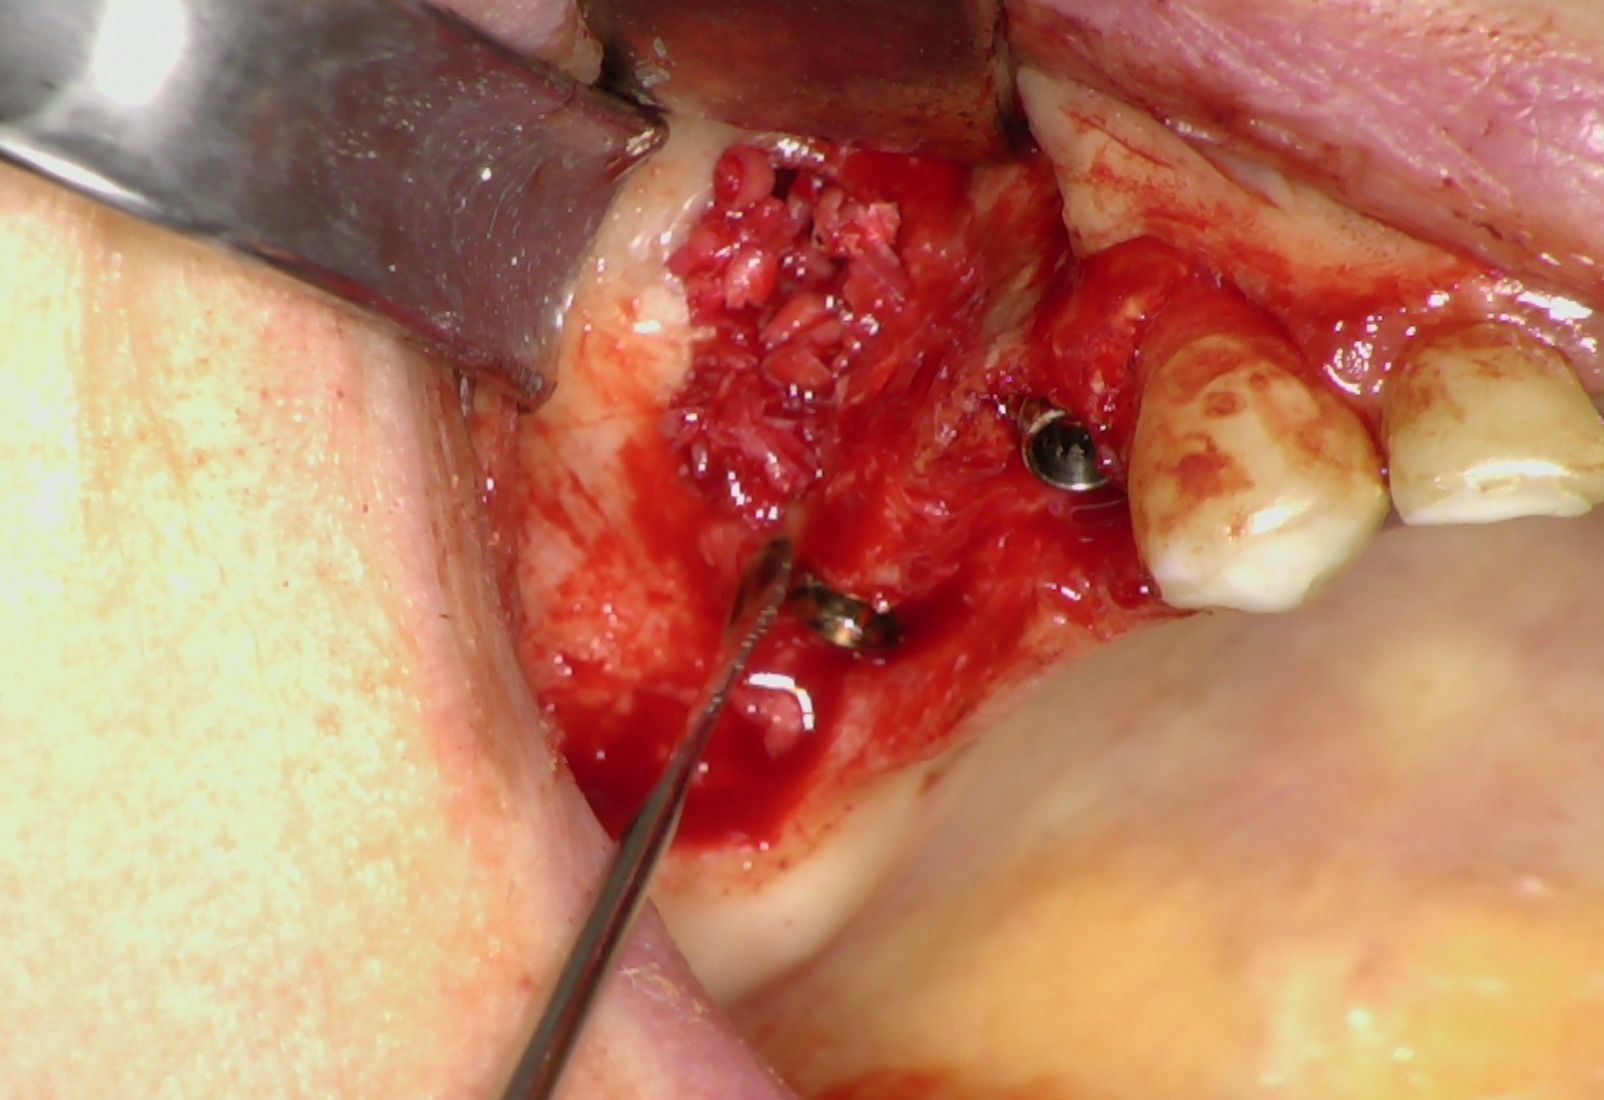

Nei settori posteriori, caratterizzati da significativa atrofia ossea e da pneumatizzazione del seno mascellare, è stato adottato un approccio transinusale. È stata pertanto realizzata una finestra laterale per consentire il sollevamento della membrana di Schneider (Fig. 3), procedura eseguita con particolare attenzione per preservarne l’integrità. Successivamente i siti implantari sono stati preparati con una traiettoria inclinata che attraversa la cavità sinusale, permettendo l'ancoraggio nell'osso basale anteriore. Sono stati quindi inseriti due impianti BT-Rhyno (Fig. 4), progettati specificatamente per l'inserimento transinusale e in grado di garantire adeguata stabilità anche in presenza di ridotto spessore osseo crestale.

Fig. 3 - Membrana di Schneider

Al termine della fase implantare è stata eseguita una rigenerazione ossea localizzata intorno agli impianti posteriori utilizzando osso autologo prelevato mediante bone scraper (Fig. 5). Questo passaggio ha consentito di colmare eventuali spazi peri-implantari, favorendo i processi di osteointegrazione e contribuendo a migliorare la prognosi a lungo termine.